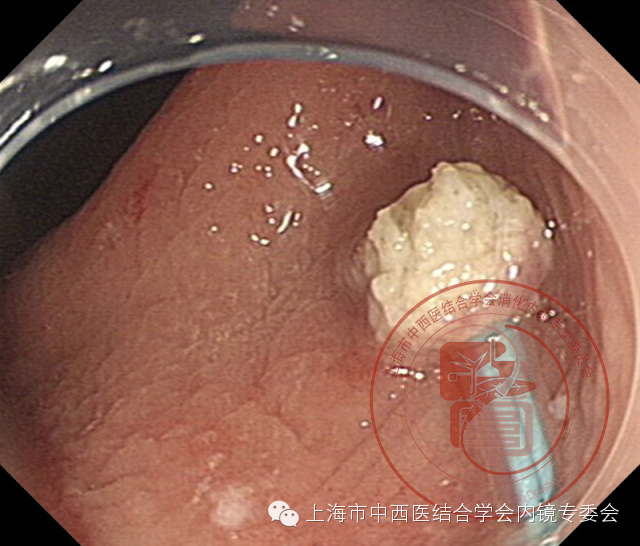

切除后创面